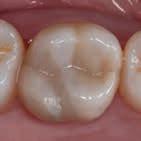

En dybtliggende amalgam-misfarvning udgør en af de mest vanskelige udfordringer ved udskiftning af restaureringer. Transcend Universal Body farven blev anvendt til at erstatte amalgamen, uden brug af blokeringsmateriale. Bemærk, hvor fremragende farven blender ind i den bevarede crista obliqua.

Før Efter